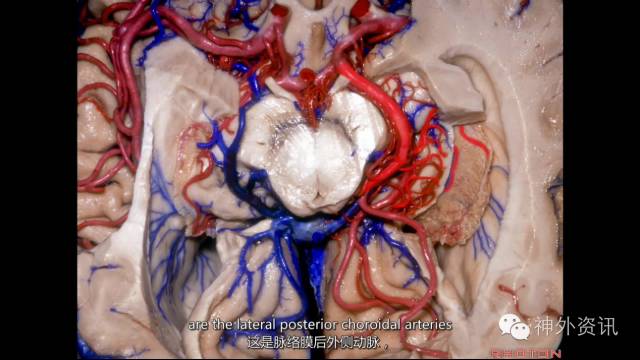

脉络膜动脉;

脉络膜动脉